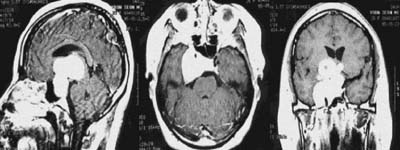

<³úÁ¤µ¿¸Æ±âÇü>

½Ã»óµ¿

ÀÎÁ¢ºÎ ºÎÀ§ÀÇ ³úÁ¤µ¿¸Æ±âÇüÀÇ MRI¿Í Ç÷°üÁ¶¿µ¼ú

¼Ò°ß

<¸ð¾ß¸ð¾ßº´(¼Ò¾ÆÁßdz)>

¿ìÃø

³»°æµ¿¸ÆÀÇ Æó»ö¼Ò°ß°ú °æµ¿¸ÆºÎÀ§ÀÇ

ÀÌ»óÇ÷°ü¸Á ¼Ò°ßÀÌ º¸À̰í ÀÖ´Ù. |